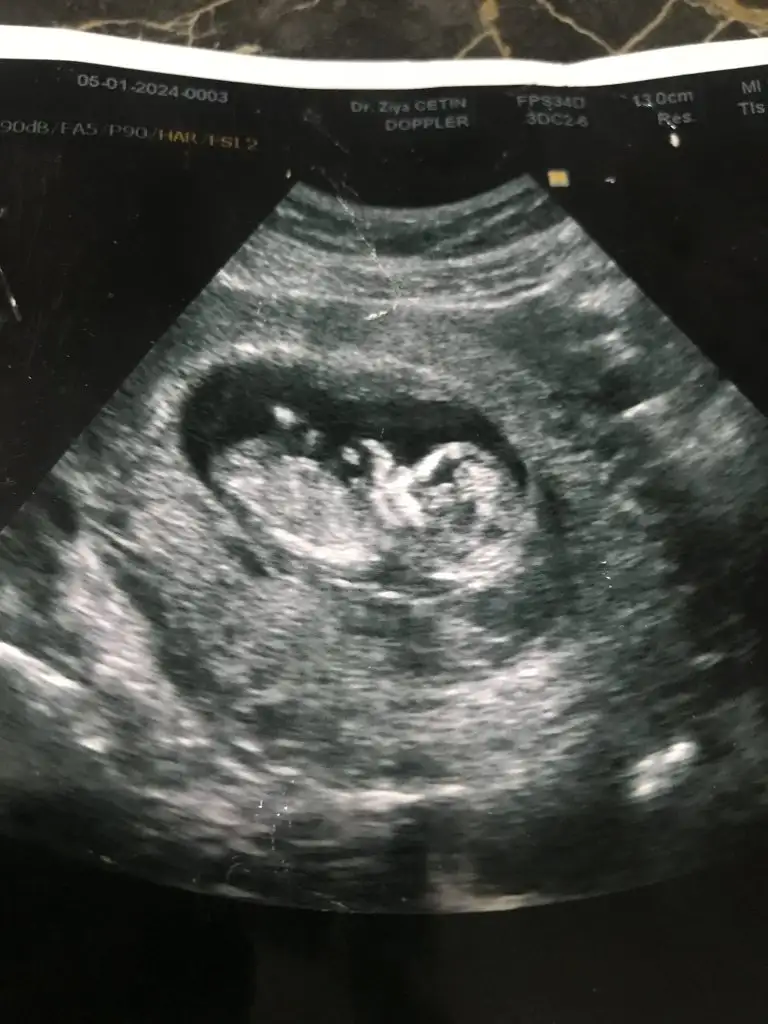

Bence erkekMerhaba benimkine de bakar mısınız vajinal ultrason

Merhaba banada yorumda bulunabilirmisiniz 12 haftalık

Bi de buna bakar mısınız 9+3Bencede bu direk erkek canım bak bu ilettiğim görüntüye çok benziyorsağlıcakla gelsi